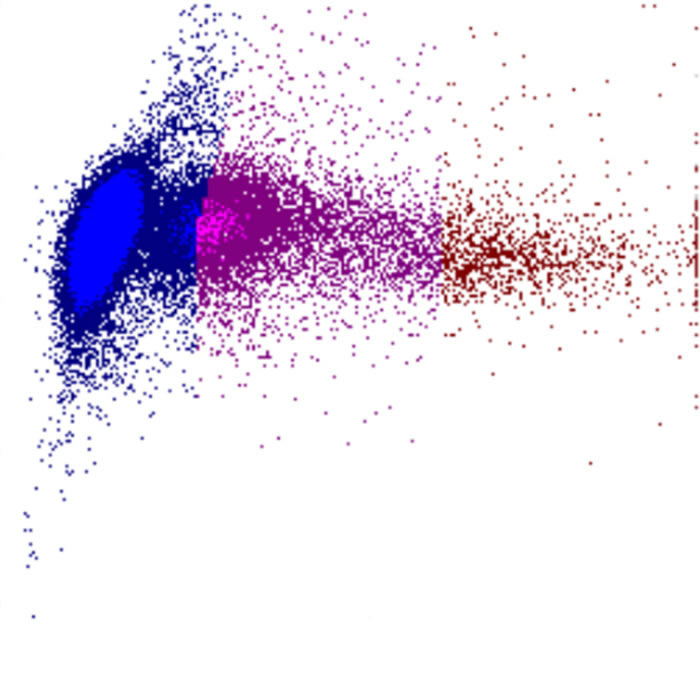

Dans cette section, vous trouverez une explication des diagrammes de dispersion (également appelés scatter ou scatterplots) issus de la série Sysmex XN/XR, avec un accent sur les canaux WDF, WNR et RET. Les scatterplots constituent la base de l’analyse différentielle des leucocytes et offrent une visualisation des populations cellulaires et de leurs anomalies.

Les diagrammes de dispersion sont un outil puissant pour le dépistage des cellules sanguines. Les motifs sont sensibles mais pas entièrement spécifiques et peuvent donc différer des exemples présentés sur ces pages. Interprétez toujours le graphique en lien avec la morphologie et les autres paramètres de laboratoire.

Selon les paramètres représentés l’un par rapport à l’autre, la combinaison de ces signaux détermine la position de chaque cellule sur le diagramme de dispersion. Cela génère des clusters caractéristiques pour les populations cellulaires normales et des motifs reconnaissables en cas d’anomalies.

Densité

La densité des points dans un diagramme de dispersion reflète le nombre de cellules présentant des caractéristiques physiques et de fluorescence similaires. Le diagramme indique ainsi non seulement la présence de populations cellulaires, mais aussi leur taille relative et leur homogénéité.

• Une forte densité de points indique une population cellulaire importante et relativement homogène

• Des motifs diffus ou dispersés peuvent suggérer une hétérogénéité, une activation ou la présence de cellules anormales

• Des déplacements, un élargissement ou un chevauchement entre populations constituent souvent des signes précoces de morphologie anormale ou de cellules rares